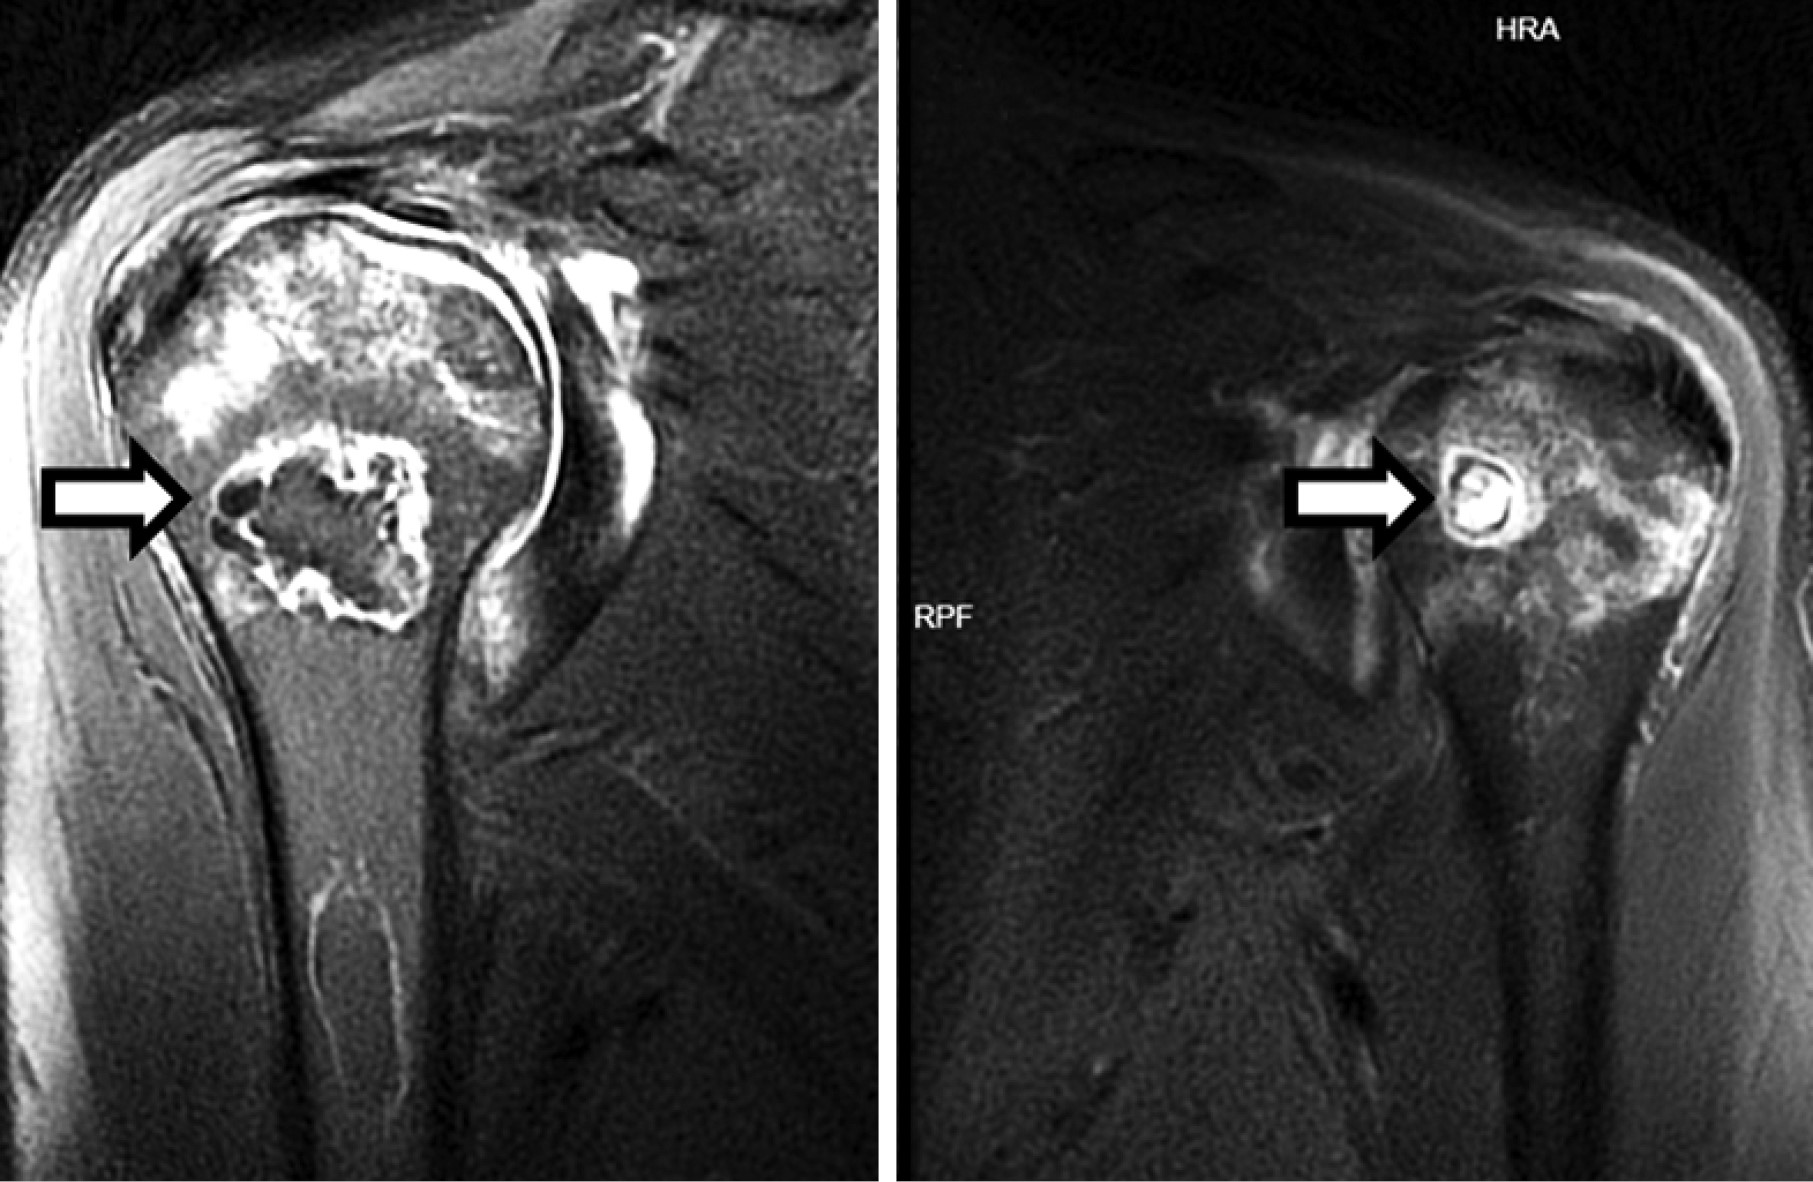

Upon admission to our clinic, the patient underwent bilateral suprascapular nerve radiofrequency ablation to manage shoulder pain. Following the procedure, he was monitored for a period of 6 months. During this follow-up period, the patient experienced sustained pain relief, with an 80% reduction in shoulder pain based on the Visual Analog Scale (VAS). Additionally, the patient’s shoulder function improved significantly, with an increase in range of motion and the ability to perform daily activities without discomfort. These clinical outcomes demonstrate the effectiveness of the procedure in providing long-term pain relief and functional improvement (Figure 3). For the persistent hip pain, bilateral Pericapsular Nerve Group (PENG) block was administered, providing an approximately 50% reduction in hip pain (Figure 4).

Figure 3. Ultrasound-guided suprascapular nerve radiofrequency ablation procedure. The white arrow indicates the targeted suprascapular nerve

Figure 4. Ultrasound-guided pericapsular nerve group block procedure. The white arrow highlights the pericapsular space being targeted to deliver local anesthetic for pain management in hip AVN